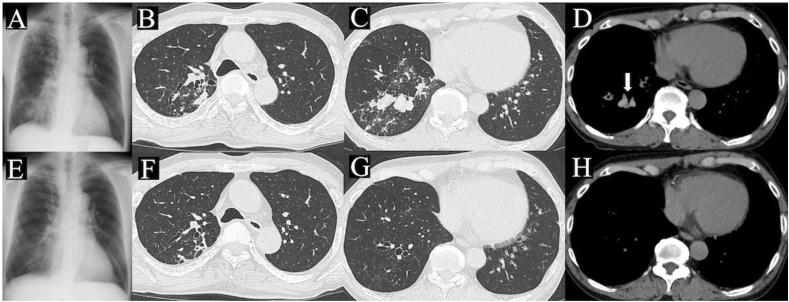

Recently, there are several reports of simultaneous allergic bronchopulmonary aspergillosis (ABPA) and (MAC) lung disease. However, the strategies for early diagnosis and appropriate treatment for patients with both ABPA and MAC lung disease have not been established. Here, we report a case with ABPA complicated by MAC lung disease, which was successfully diagnosed and treated by simultaneous administration of systemic steroids and antimycobacterial drugs. Bronchoscopy can be useful in the diagnosis of such cases. Furthermore, in a patient with concurrent ABPA and MAC lung disease, simultaneous treatments for both diseases could reduce both diseases.

最近,有几篇关于同时发生变应性支气管肺曲霉病(ABPA)和非结核分枝杆菌(MAC)肺病的报道。然而,针对同时患有ABPA和MAC肺病患者的早期诊断和恰当治疗策略尚未确立。在此,我们报告1例并发MAC肺病的ABPA病例,该病例通过同时给予全身用类固醇和抗分枝杆菌药物而成功获得诊断和治疗。支气管镜检查对此类病例的诊断可能有用。此外,对于同时患有ABPA和MAC肺病的患者,对两种疾病同时进行治疗可使两种疾病均得到缓解。